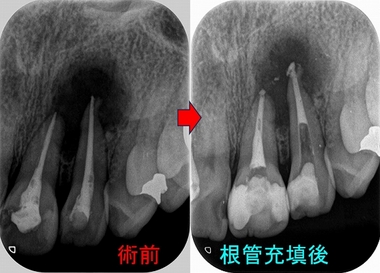

書籍詳細「長期経過症例から紐解く根尖病変と骨縁下欠損」 | フォル。書籍詳細「長期経過症例から紐解く根尖病変と骨縁下欠損」 | フォル。長期経過症例から紐解く根尖病変と骨縁下欠損。「長期経過症例から紐解く根尖病変と骨縁下欠損 = Treatment trends and measures of periapical lesion and infrabony defect : その傾向と対策」倉富 覚、 / 下川 公一定価: ¥ 260001度も読んでいない新品ですが素人の自宅保管になります。他にも多数出品しておりますので是非宜しくお願い致します。間違った根管治療で大きな根尖病変(膿) - EE DENTAL_Blog。中身は読んでいないので新品同様綺麗ですが、表紙やカバーには新品ですが保管による小傷や汚れがある場合がありますので完璧な新品を求めている方は落札をご遠慮下さい。化学・バイオ特許の出願戦略 改訂11版。神経内科専門医試験問題 解答と解説<第1・2集>。#倉富覚、 #倉富_覚、 #下川公一 #下川_公一 #本 #自然/医療・薬学・健康

• 間違った根管治療で大きな根尖病変(膿) - EE DENTAL_Blog